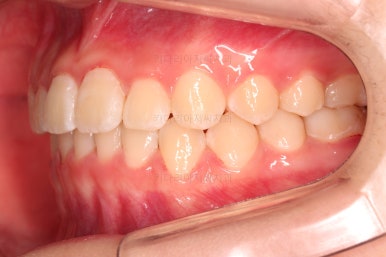

✅ 앵글씨 2급 부정교합

이번 환자분은 앵글씨 2급 부정교합이었는데요.

정상교합에 비해서 윗니가 상대적으로 앞에 아랫니가 상대적으로 뒤에 위치한 부정교합이 앵글씨 2급 부정교합입니다.

이번 환자분은 어금니가 위아래가 지그재그 서로 엇갈려 꽉 끼이는 교합이 아니라 1대1로 치아가 부딪혀 있는 상태였습니다.

이런 경우는 치아가 마모가 매우 잘되고 치아의 잇몸 근처 부분이 빨리 패여져 나가거나 잇몸 퇴축도 빨리 오게 됩니다. 물론 씹는 기능도 떨어지게 마련이고요.

장치 부착 직후의 눈에 보이는 모습과 옆라인의 변화 확인해 주시고요.

이번 환자분은 장치를 부착했다고 해서 옆라인이 거의 차이가 나지 않는 케이스였습니다.

가지런하고, 교합도 좋으며 과개교합이나 앵글씨 2급 부정교합 부분도 완벽히 좋아졌습니다.

자연스럽게 중앙선도 매우 좋아졌고요.